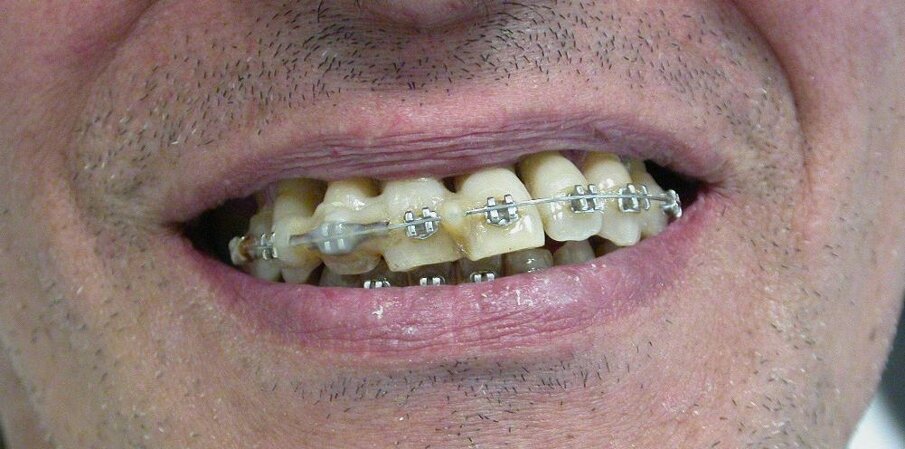

Iniziano le terapie (ablazioni tartaro, ortodonzia, scaling e root planing, curettages gengivali, farmaci nelle tasche, laser, test microbiologici ripetuti e trattamenti endocanalari) che si protraggono da febbraio 2012 al maggio 2015. Costo? Circa 11.500 euro, ma inizialmente i risultati ci sono: il paziente sta meglio, l’alitosi si ridimensiona, i denti perdono l’iniziale mobilità e si sono rapidamente allineati, anche se il livello di igiene domiciliare non è proprio migliorato.

Poi, però, la situazione cambia: i denti si sventagliano, alcuni risultano avulsi dagli alveoli (12, 22, 15, 25) restano in bocca solo perché attaccati al filo ortodontico. Altri si muovono più di prima. Poi qualche dente viene spontaneamente “sputato”. Il dottore da la colpa alla scarsa igiene domiciliare e propone alcune estrazioni (12, 22, 15, 25), interventi di chirurgia parodontale, altra endodonzia e protesi, con ulteriore richiesta di € 15 mila euro.

Alla visita del CTU le condizioni cliniche sono peggiori di quelle oggettivate (Figg. 1-4) alla fine del rapporto. Il riconoscimento di concorrenza di cause porta ad accollare a YZ solo parte dei danni rilevati (danno biologico 1% e ITP al 10% per 50 giorni), ma l’inadempimento fa riconoscere anche l’obbligo di rendere quanto percepito per prestazioni inutili e non indicate. Dovrà quindi restituire di tasca propria competenze per almeno 10.000 euro oltre alla franchigia prevista dal contratto di polizza in materia di risarcimento e alle spese legali. Nelle incaute promesse il Giudice riconosce, inoltre, un grosso vizio di consenso.